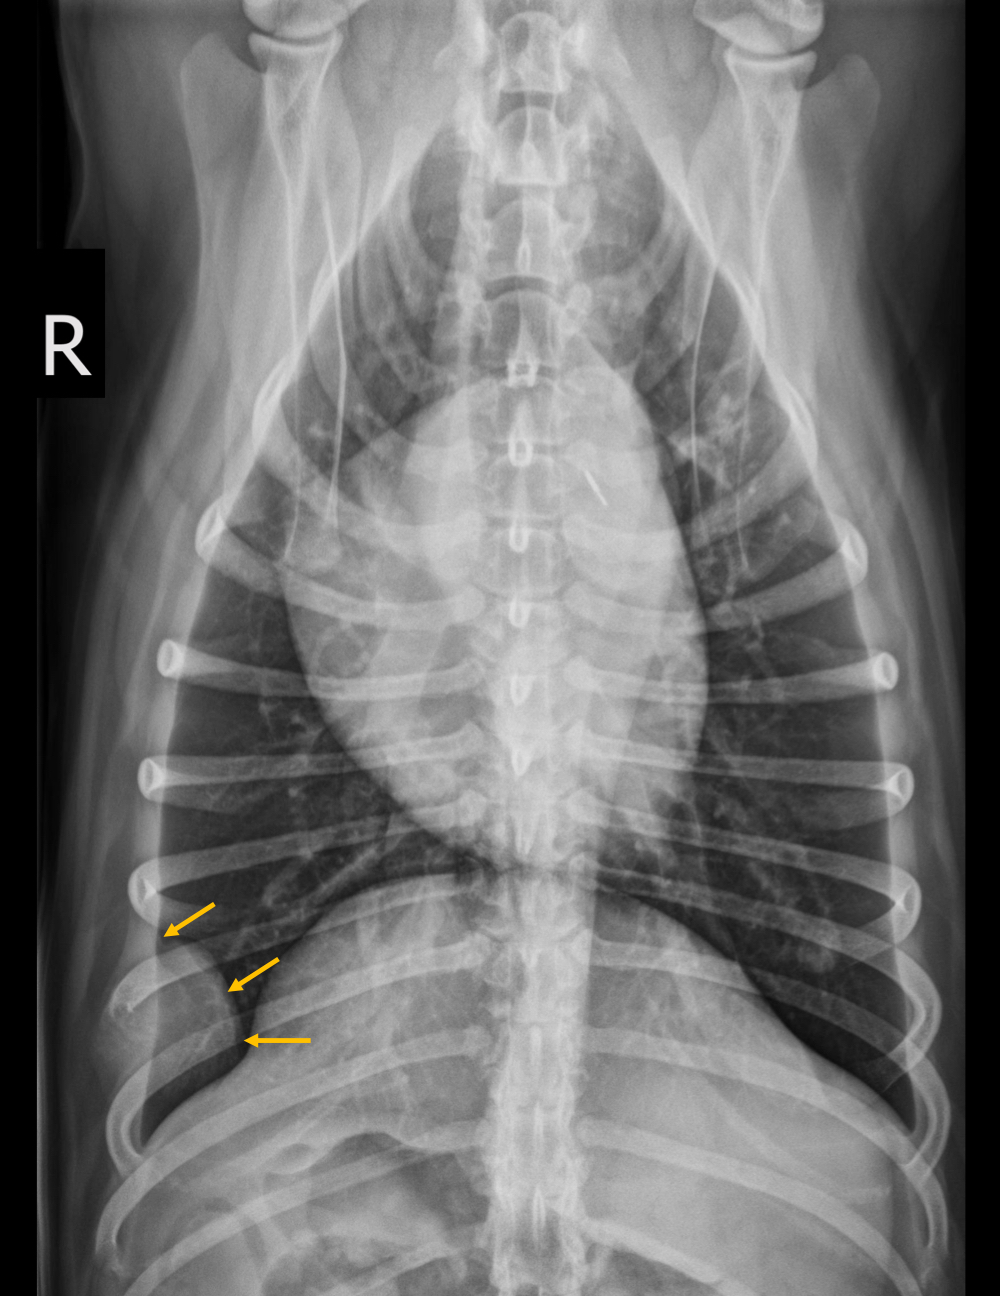

Q

What is seen in this radiograph?

A

expansile soft tissue lesion —> rib lysis, loss of cortices